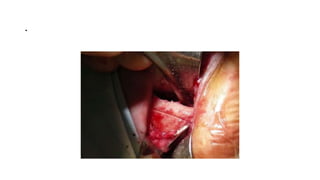

Lateral canthal incision